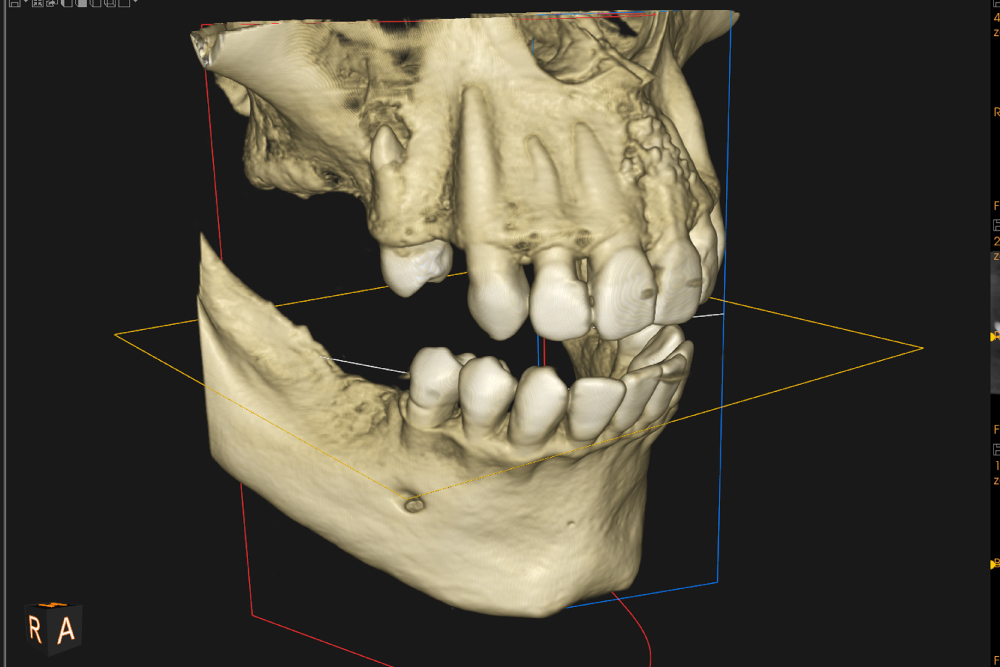

当院では、3Dで骨や神経の位置を確認できるCT(歯科用CBCT) を導入しています。親知らずは、下あごの大きな神経(下歯槽神経)の近くに位置することがあり、2Dのレントゲンだけでは正確な距離がわからないケースがあります。CTで立体的に確認することで、

神経との距離

神経との距離

歯根の形・向き

歯根の形・向き

骨の厚み

骨の厚み

埋まっている深さ

埋まっている深さ

リスクの有無

リスクの有無

などを事前に把握し、安全で痛みに配慮した処置を行います。